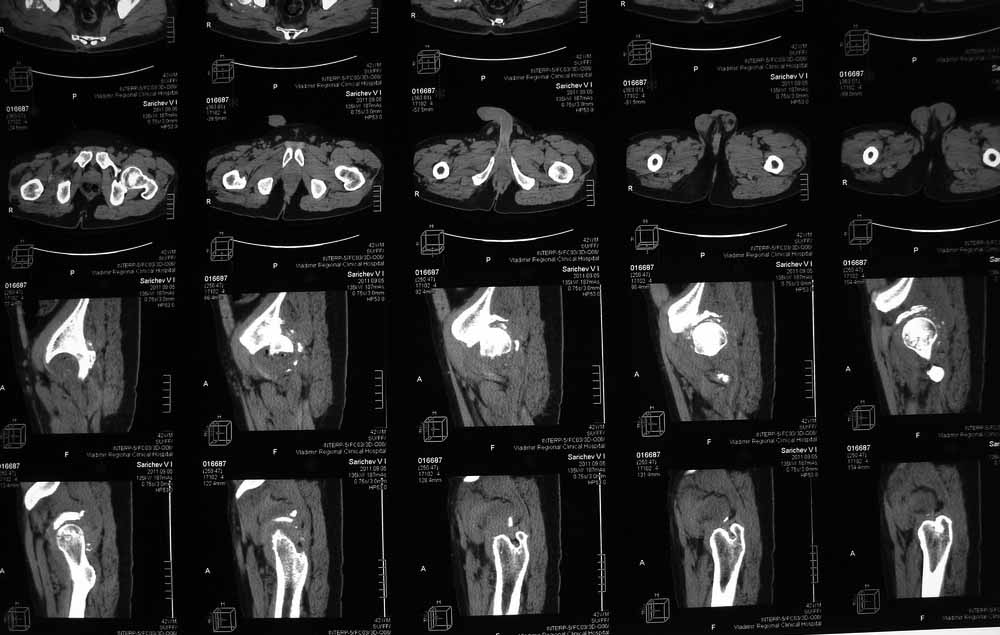

42 года, майор запаса. Травма от 20.06 - ДТП. Лечился в гражданском ЛПУ. Вывих бедра диагностирован только 4 недели спустя. "Тянулся", неоднократно - попытки закрытой репозиции. Попытка открытой репозиции - без результата. Потом опять пытались закрыто, сказали, что вправили, тянулся. После снятия ССВ - опять вывих. Поступил к нам. Сейчас - СРБ больше 10, в ОАК - воспаление. Местно - головка кзади и кверху, укорочение 7, голова подвижна. Отек, незначительная боль в в/3 бедра. Пассивно из наружной ротации выводится, активных движений в ноге нет. Рубец по наружной поверхности верхней трети бедра, без воспаления. Каким образом выполнялось открытое вправление - данных нет. Окончательно снят с вытяжения 2 недели назад.

Структуру головки не очень хорошо видно, есть перелом нижнего отдела головки БК, сломанный задний край небольшой. Срок после травмы 4 недели, молодой возраст. Есть смысл синтезировать ВВ, а дальше посмотреть. Будут проблемы - легче будет протез ставить, ну а если лет 8-10 сустав поработает, то и это хорошо. Если вы уж решили делать протезирование, не мудрите, вполне можно обойтись стандартной вертлужной впадиной с укреплением ее винтами.

Вот еще сканы.

В этой ситуации предпочел бы эндопротез, шансы на жизнеспособность головки в таком сроке вывиха исчезающе малы, попытка синтезировать задний край в этих же сроках (ретракция мышц, рубцы) скорее всего приведут к его девитализации с последующим аваскулярным некрозом. Выбор вертлужного компонента проще планировать после 3D, скорее всего можно будет обойтись стандартными предложением, возможно, с котилопластикой.